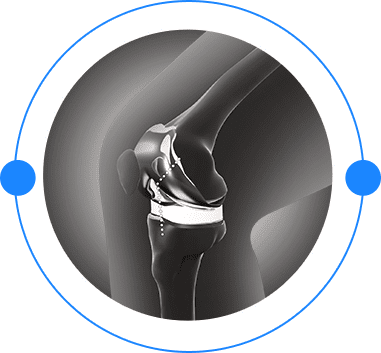

Robotic and Conventional Joint Replacement